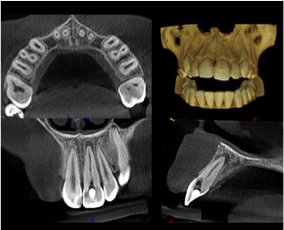

We are constantly striving to improve our endodontic practice to continually improve for our patients. The Carestream 8100 ‘Cone Beam’ CBCT machine provides a two-in-one solution (3D scan and Panoramic image) with access to powerful, focused-field 3D images and offers unprecedented x-rays views of the oral cavity. The Carestream 8100 has the smallest voxel size on the market at only 76 microns while most other CBCT machines are 125 microns or larger. The anatomical detail and viewing capabilities of 3D imaging offer a wide range of diagnostic possibilities.

When a patient is referred to our practice, they receive the best possible service with the top technology in the industry. A CBCT scan provides the following advantages:

- Diagnosis and Canal Morphology

- Non-endodontic Pathoses

- Root Fractures

- Internal Resorption

- Invasive Cervical Resorption

- Presurgical Anatomic Assessment

- Diagnosis of a Failed Endodontic Tx